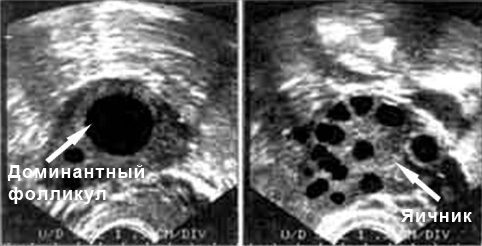

Признаки овуляции на УЗИ

Как врач может определить, что овуляция состоялась? На экране ультразвукового аппарата появятся признаки, подтверждающие выход яйцеклетки.

- На третьем визите к специалисту были выявлены созревающие фолликулы;

- зафиксирован разрыв фолликула;

- за маткой было обнаружено скопление жидкости;

- после разрыва фолликула УЗИ показало увеличение желтого тела;

- отсутствие доминантного фолликула является одним из основных признаков овуляции.

Расшифровка результатов

Все результаты будет интерпретировать квалифицированный специалист. Он знает нормы показателей для каждого этапа цикла и анализирует отклонения от этих норм. Ниже представлены нормы, которые можно сопоставить со своими результатами, чтобы понять, есть ли проблемы с овуляцией.

- Фаза роста фолликула.

- 1-8 день: доминантный фолликул отсутствует;

- 8-12 день: на УЗИ он виден, размер составляет 10 мм;

- 12-14 день: размер достигает 15 мм;

- 14-15 день: это период перед овуляцией, когда фолликул достигает 21 мм.

- Овуляция:

- В фолликуле наблюдается яйценосный бугорок;

- Стенка фолликула утолщается;

- После овуляции фолликул больше не определяется;

- За маткой может быть немного жидкости.

- Лютеиновая фаза – это процесс формирования желтого тела. Если зачатие произошло, его размер составит 18 мм. Если он превышает 23 мм, это может указывать либо на беременность, либо на наличие фолликулярных кист.

- Менструация. На УЗИ видны небольшие фолликулы, которые едва достигают 8 мм.